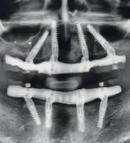

Neun von zehn Personen, die Kopfschmerzen kennen, leiden an Migräne oder Spannungskopfweh. «Einseitige, pulsierende Kopfschmerzen, die sich bei körperlicher Aktivität verstärken, das ist typisch für Migräne», sagt Stefan Maydl, Facharzt für Allgemeinmedizin, Medbase Wil Friedtal SG. Häufig kommen noch Übelkeit, Erbrechen, Licht- und Geräuschempfindlichkeit dazu.

85 Prozent der von Migräne Betroffenen sind Frauen. Bei einem Drittel beginnt die Migräne mit der ersten Menstruation. Nach der Menopause lässt die Migräne bei zwei Dritteln wieder nach. «Treten nach dem 50. Geburtstag zum ersten Mal migräneartige Kopfschmerzen auf, sollten Ursachen wie hoher Blut- oder Augendruck bei einer ärztlichen Untersuchung ausgeschlossen werden», sagt Maydl.

Im Gegensatz zur Migräne treten Spannungskopfschmerzen oft beidseitig auf und verschlimmern sich durch Bewegung nicht. «Spannungskopfschmerzen können von einer schlechten Haltung am Arbeitsplatz herrühren, aber auch von einer Zahn- oder Nasennebenhöhleninfektion», so Maydl.

Vorsicht bei häufigem Kopfweh: Wer drei Monate lang an mindestens zehn Tagen monatlich Akutmedikamente gegen Schmerzen einnimmt, riskiert eine Verschlimmerung oder sogar ein chronisches Auftreten von Kopfschmerzen. Dabei handelt es sich um einen sogenannten MÜKS: einen Medikamenten-Überkonsum-Kopfschmerz.

5Die meisten Migräneattacken gibt es an Samstagen, weil sich bei vielen dann der Rhythmus ändert. Um Migräneanfällen vorzubeugen, ist ein gleichbleibender Schlafund Essensrhythmus wichtig. Das bedeutet, dass es Betroffenen helfen kann, möglichst auch am Wochenende zur gleichen Zeit wie werktags aufzustehen.

Gegen chronische Spannungskopfschmerzen helfen Dehnübungen sowie Stärkung der Nacken- und Schultermuskulatur. Auch Ausdauersport tut gut. «Ich empfehle dreimal wöchentlich 45 Minuten», sagt Maydl. Wem Sport weniger liegt, kann den Schmerzen mit täglichen Entspannungsübungen vorbeugen.

Mehr als fünf Tassen Kaffee pro Tag können Migräneanfälle begünstigen. Der goldene Mittelweg ist der richtige. «Wer regelmässigen Kaffeekonsum gewohnt ist, könnte durch einen abrupten Stopp ebenfalls eine Migräneattacke riskieren», so Maydl.

War es die Schokolade, das Wetter oder doch das anstrengende Training, das die Migräne verursacht hat? Vielleicht. Die vermuteten Auslöser sind manchmal die Vorboten einer nachfolgenden Attacke. Ein Kopfschmerz-Tagebuch kann helfen, die Anzeichen genauer zu erkennen.

Kopfschmerz-Check in Medbase Apotheken

Die Medbase-Apotheken bieten einen KopfschmerzCheck an: Auf eine vertiefte Analyse der Schmerzen folgen in einem persönlichen Gespräch Beratung und Infos zu möglichen Therapieansätzen.